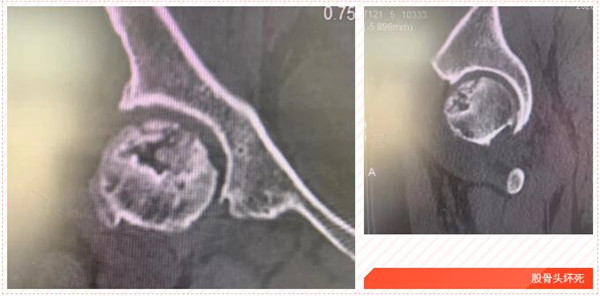

五年前,家住岱山的洪女士發(fā)覺自己的髖部經(jīng)常疼痛,有時候活動都受影響,特別時久行后更是疼痛難忍,便到我市某院就診,經(jīng)檢查診斷為“雙側股骨頭壞死”,予以口服藥物等保守治療,可并沒有好轉。

2017年5月,在朋友的建議下,洪女士來到我院,經(jīng)CT診斷雙側股骨頭無菌性壞死。便在危立軍副院長的建議下,做了左髖關節(jié)置換術。術后,洪女士恢復良好。